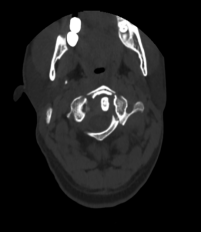

在仔细研究了患者的片子后,发现寰椎前后弓四处骨折,双侧侧块漂浮,寰齿间隙增大,后弓的骨折块还陷入到椎管内。尽管没有造成颈髓损伤,但稍有移动就可能导致瘫痪甚至死亡,因此姜主任确定该患者的最佳治疗方案为寰枢椎内固定手术。

在麻醉手术科的配合下,有了高精尖的第二代“O”-臂机的辅助,加之姜主任丰富的临床经验,手术非常顺利。第二代“O”-臂机扫描颈椎三维重建显示寰椎移位的骨块复位完成,寰枢椎椎弓根螺钉位置良好。术后,患者颈部疼痛症状明显改善。